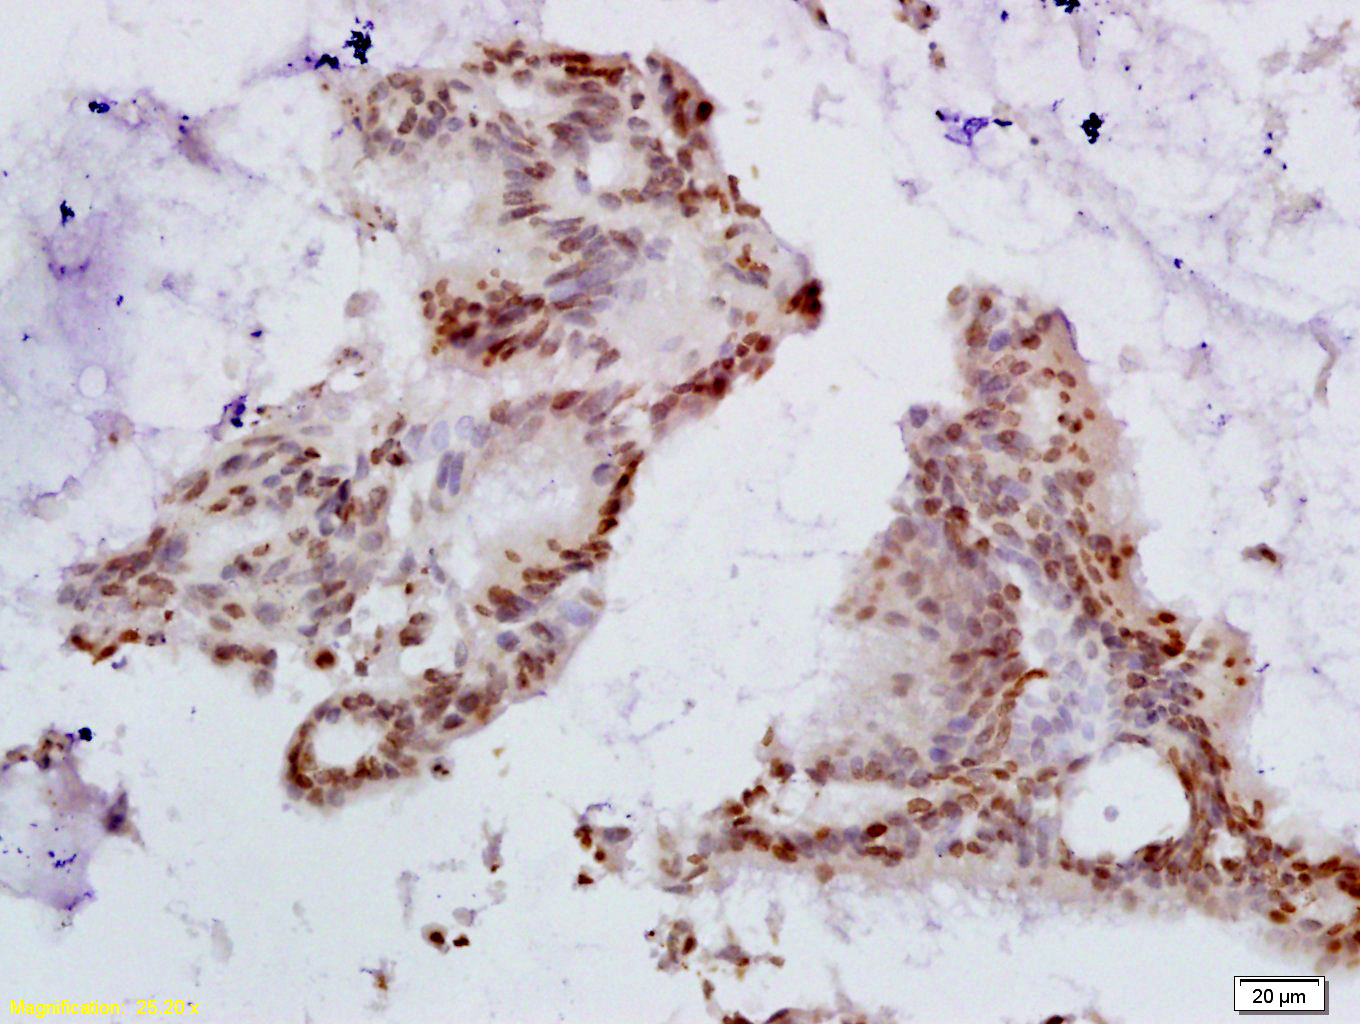

Tissue/cell: human colon carcinoma; 4% Paraformaldehyde-fixed and paraffin-embedded;

Antigen retrieval: citrate buffer ( 0.01M, pH 6.0 ), Boiling bathing for 15min; Block endogenous peroxidase by 3% Hydrogen peroxide for 30min; Blocking buffer (normal goat serum,C-0005) at 37℃ for 20 min;

Incubation: Anti-HPV16 E6+HPV18 E6 Polyclonal Antibody, Unconjugated(bs-1719R) 1:200, overnight at 4°C, followed by conjugation to the secondary antibody(SP-0023) and DAB(C-0010) staining